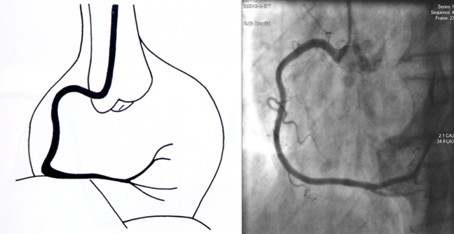

左冠造影体位:右前斜 头位(右肩位,rao cra):从受检者右肩观测心脏;左

图片尺寸946x467